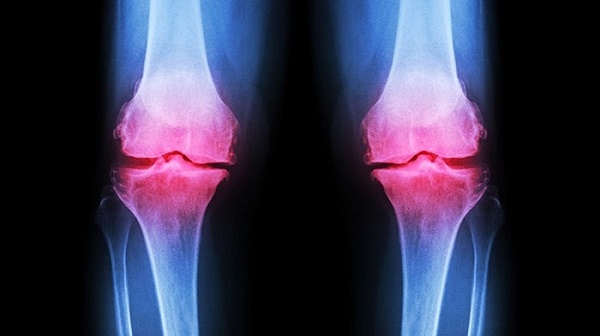

- Nếu không điều trị kịp thời, bệnh nhân sẽ đối diện với nguy cơ tàn phế (ảnh minh hoạ)

Nếu không được điều trị kịp thời, người bị thoái hóa khớp có nguy cơ tàn phế rất cao. Theo WHO, khoảng 80% bệnh nhân thoái hóa khớp có những hạn chế trong vận động và 25% không thể thực hiện các hoạt động thường ngày.